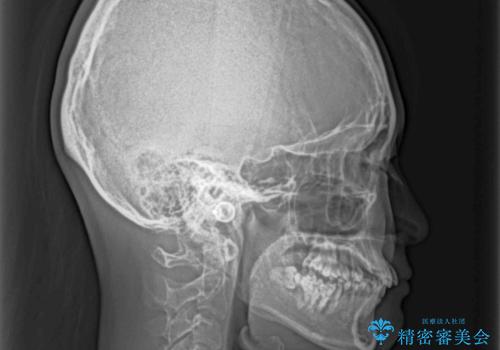

- 前歯のデコボコと奥歯の不正咬合を気にして来院された患者様です。

左右の大臼歯が全て鋏状咬合(シザーズバイト)になっており、治療が難航することが予想されましたが、インビザラインにより治療を行うこととしました。

最難関と思われたシザーズバイトは比較的短期間で解消されました。

しかし、治療中に2度の出産を経験され、治療期間は長くなってしまいましたが、咬みやすく、清掃しやすい歯列を獲得することができました。